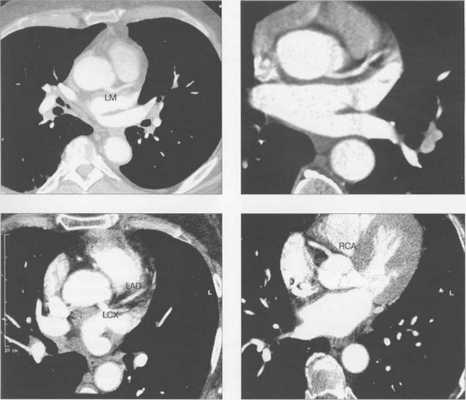

МСКТ в условиях внутривенного болюсного контрастирования позволяет визуализировать коронарные артерии (МСКТ-коронарография). Анализ состояния коронарных артерий выполняется сначала на аксиальных срезах (рис. 9.35). В постпроцессинговой обработке изображений используются различные виды реконструкций: многоплоскостные реформации (MPR), проекция максимальной интенсивности (MIP), трехмерные (VRT) (рис. 9.36).

Рис. 9.35. МСКТ-коронарограммы. Поперечные срезы.

Здесь и на рис. 9.36:

LM — ствол левой коронарной артерии, LAD — левая передняя нисходящая артерия, LCX — левая огибающая артерия, RCA — правая коронарная артерия.